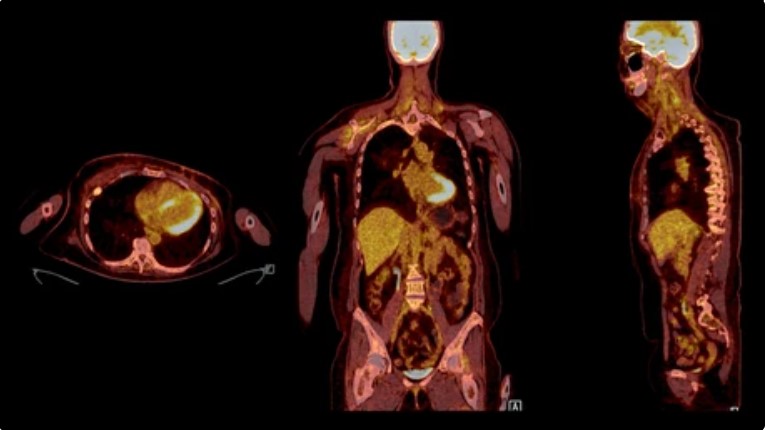

Radioaktive isotoper er et område der i en eksplosiv vækst internationalt, primært drevet af moderne landvindinger inden for elektronik, kemi og biomedicin. Væksten og de udvidede muligheder for behandling på kræftområdet går hånd i hånd med nye produktionsmetoder for kunstig radioaktivet. Hidtil utilgængelige isotoper kan pludselig bringes i spil.

Mikael Jensen vil, med udgangspunkt i sin egen arbejdserfaring vise den direkte linje fra Hevesy og Bohrs første brug af neutronerne fra radium-kilder via de tre moderne cyklotroner på Risø og til den voksende medicinske produktion på de store europæiske forskningsanlæg: CERN, PSI, Grenoble, og med tiden måske også på ESS i Lund.